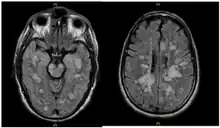

| Fulminating ADEM showing many lesions. The patient survived, but remained in a persistent vegetative state | |

ADEM produces multiple inflammatory lesions in the brain and spinal cord, particularly in the white matter. Usually these are found in the subcortical and central white matter and cortical gray-white junction of both cerebral hemispheres, cerebellum, brainstem, and spinal cord,[16] but periventricular white matter and gray matter of the cortex, thalami and basal ganglia may also be involved.